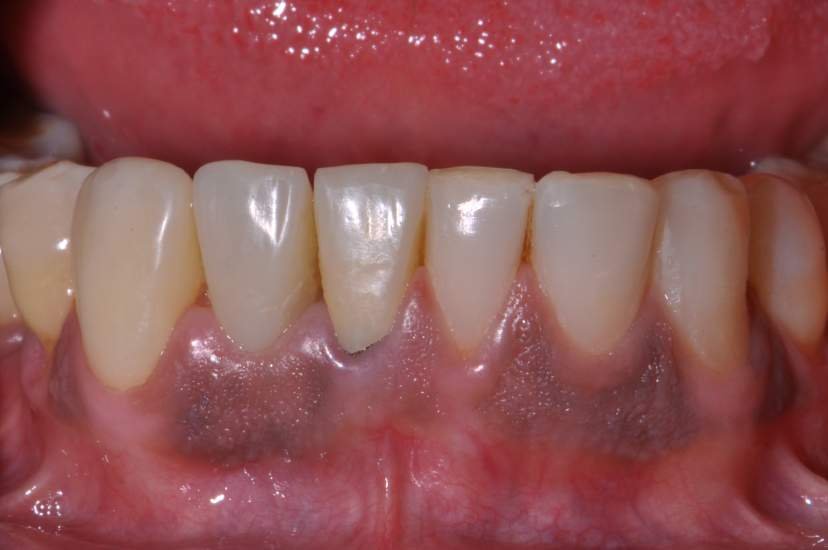

CASO CLÍNICO

Paciente com perda do incisivo central inferior do lado direito, utilizando uma prótese fixa em zircônia com estética e adaptação deficientes.